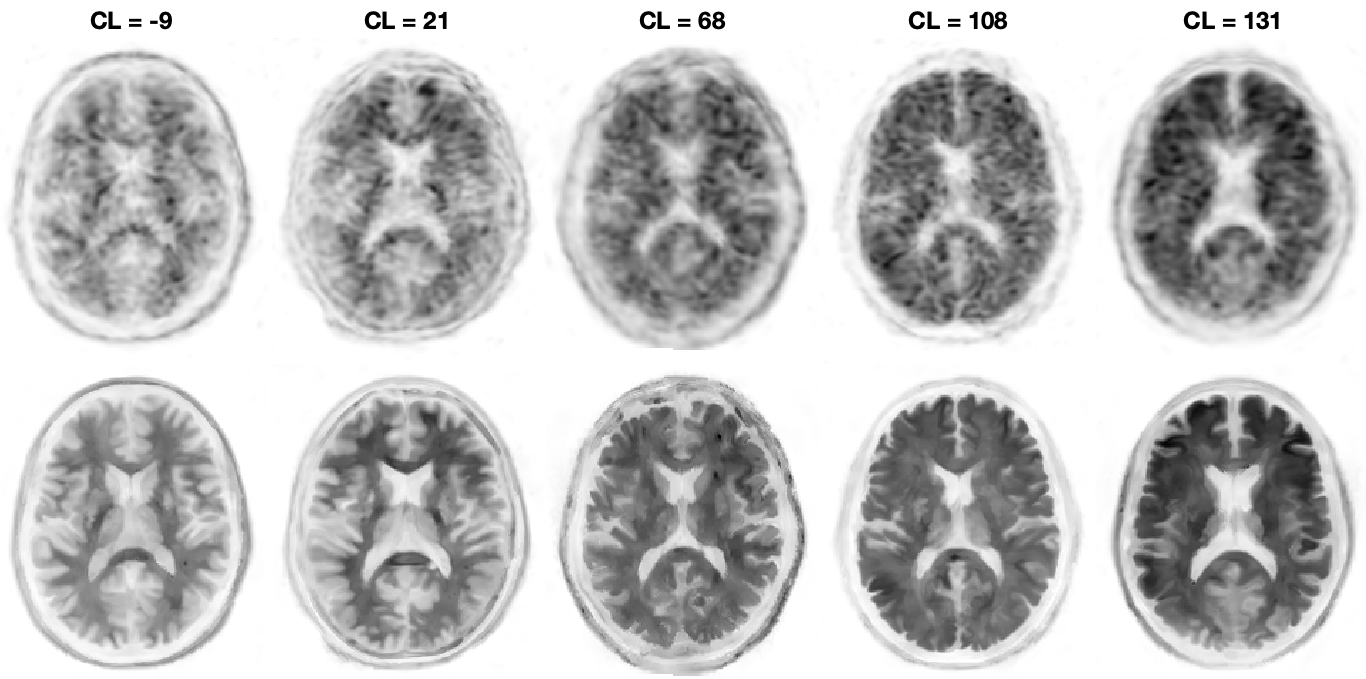

Figure: Coregistered conventional PET and MICSI-PET amyloid images across a range of amyloid burdens, highlighting differences in apparent cortical sparing: left, amyloid-negative with strong gray/white contrast; right, amyloid-positive with reduced gray/white contrast.

MICSI-PET is a turnkey upgrade that dramatically enhances PET image quality by using the MRI as an anatomical guide. This process does not require any additional imaging as all patients should have received an MRI prior to amyloid PET imaging. Operationally, this upgrade removes the primary barrier for scaling Alzheimer’s therapies by (1) enabling high-end PET imaging on low-end or aging PET scanners; (2) enabling shorter PET examinations leading to greater throughput; (3) minimizing ambiguity of positive/negative amyloid PET imaging by showing clearer boundaries between gray and white matter: